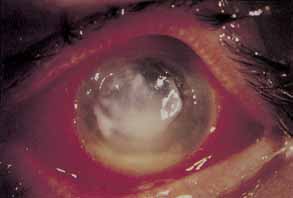

STROMAL EDEMA Corneal hypoxia leads to accumulation of lactate in the stroma.9 The presence of increased stromal levels of lactate increases the osmotic pressure within the stroma, and edema ensues.108 There is good evidence that the attendant stromal acidosis impairs endothelial cell function, which in turn exacerbates stromal swelling.109 Corneal stromal edema results in corneal thickening, stromal striae and folds, corneal distortion, and increased light backscattering secondary to disruption of the regular pattern of collagen lamellae.9,110,111 The edema may be irreversible in eyes in which the endothelium is severely compromised.112 Rarely with modern lenses epithelial edema, or Sattler's veil, produces glare and halos around bright lights.111 Because stromal thinning is noted with long term soft lens wear, swelling in these patients may only bring the corneal thickness into the normal range.9 The minimum oxygen transmissibility of a contact lens required to prevent edema both in the open- and closed-eye situations may be calculated experimentally.113,114 Clinically, however, there is a significant intersubject variability in edema thresholds for the same lens material and thickness.115,116 To provide a safe margin for the vast majority of the lens wearing population, it is important to maximize the oxygen transmissibility of contact lenses, particularly those for extended wear.117 In some cases cessation of extended lens wear is necessary to avert recurring bouts of blurred vision upon awakening. Persistent stromal edema over time may have adverse effects on corneal endothelial cells, a subject to be discussed later in this chapter. DEEP STROMAL NEOVASCULARIZATION AND HEMORRHAGE Corneal hypoxia related to contact lens wear may induce deep stromal neovascularization in both rigid and soft lens wearers.9,118 In rigid lens wearers, PMMA use is a significant risk factor. Low oxygen permeable and thick (i.e., aphakic) soft lenses are more likely to cause this response.119,120 Eyes that have suffered surgical trauma are also at risk.9,119 Cessation of lens wear, reduction in wearing time, or change to lenses with higher dK/L values slow or halt the progression of neovascularization. More creative treatment involves exposure of the ocular surface to increased concentrations of oxygen.118 The vessels will not recede but shrink to form “ghost vessels.” Complications related to stromal neovascularization are rare and include intrastromal hemorrhage and interstitial keratitis.9 Intrastromal hemorrhage most commonly occurs in the setting of aphakic, extended, soft lens wear but has been reported with daily cosmetic lens wear as well.121–123 The hemorrhages clear leaving varying degrees of attendant visual loss, and at least one patient required corneal transplantation to restore vision.122 Circinate-pattern lipid exudate surrounding stromal vessels has been described in a group of five daily soft lens wearers.124 These infiltrates differ from classic interstitial keratitis because they did not increase with time, were not associated with an inflamed eye, and did not respond to topical corticosteroids. STROMAL OPACITIES Stromal opacities may be seen with or without concomitant stromal vascularization.9 In contrast to superficial, deep stromal vascularization more commonly results in permanent corneal scarring. Superficial stromal opacities rarely occur in association with generalized superficial ocular inflammation, but recovery from the causal insult generally precedes dissolution of stromal scarring.125 An unusual arcuate superficial stromal opacity of the superior cornea has been reported in a small group of soft, cosmetic, daily lens wearers.126 The opacities were felt to result from tight eyelids, although a case could be made for the type of lens as cause.127 Most anterior stromal opacities are associated with soft lens wear, except for those found in keratoconus, which may occur both with and without contact lens wear. Keratoconus patients most likely to develop stromal opacities are those fit with large flat lenses instead of small lenses with apical clearance.128 Deep stromal opacities have been reported in association with both rigid and soft lens wear.129 These whitish, pre-Descemet's opacities form bilaterally in the central corneas of long-term contact lens wearers and are associated with marked endothelial polymegathism. In some cases the opacities may cause visual loss but will gradually disappear with cessation of lens wear or change to a more oxygen permeable lens. With the different types of superficial opacities and deep stromal opacities, thimerosal toxicity, allergy, and chronic hypoxia have been implicated as potential causes.9,125–129 STERILE INFILTRATES Sterile corneal infiltrates associated with contact lens wear are generally multiple, small, anterior stromal infiltrates found most often at the corneal limbus but also in clusters in the central cornea (Fig. 4).130–132 Rarely the epithelium alone may be involved and is commonly intact over stromal infiltrates. The anterior chamber may show mild to severe cellular reaction.130 Corneal infiltrates related to extended soft lens wear tend to form near the superior limbus.133 These infiltrates must be distinguished from their infectious counterparts, including chlamydia, by careful historical consideration and clinical examination.131 If there is any doubt regarding the etiology of the infiltrates, scrapings for stain and culture should be taken, followed by appropriate broad-spectrum topical antibiotic therapy. Using rigid gas permeable lens wear as the referent, soft lens wearers and particularly extended soft lens wearers carry a significantly higher risk of developing sterile infiltrates.6,9,130,134 PMMA lens wearers are the least likely to suffer this complication.134 A longer duration of soft lens wear provides a proportionately increased risk of developing these infiltrates.132,135 The rate of sterile infiltrates per year for disposable extended soft lens wear in a prospective study was as high as 7%, suggesting that disposable lenses are not the solution to this problem.136 Daily disposable soft lenses or soft silicone hydrogel lenses afford the lowest rate of peripheral infiltrates for soft lens wear.22,132 Various theoretic causes include chemical hypersensitivities to thimerosal and chlorhexidine, exposure to a variety of environmental toxins through digital contamination, improper enzyme use, staphylococcal lid disease, and bacterial contaminants of contact lens cases.130,137 Antigenic debris held chronically against the corneal surface has been cited as a potential basis for sterile infiltrates, particularly with extended soft lens wear.130–134 Required therapy consists of discontinuing lens wear and treating cautiously with topical corticosteroids, a practice that necessitates frequent initial examinations.130 Lens wear should cease until there is complete resolution of all infiltrates and adequate corticosteroid taper. Recurrences may be avoided by careful review of contact lens care and handling, cessation of suspected offending chemicals, insistence on clean contact lens cases and treatment of any associated staphylococcal lid disease. Recurrent infiltrates associated with extended soft lens wear may require the use of soft or rigid daily wear lenses. Daily disposable and silicone hydrogel soft lenses are an excellent strategy for prevention in susceptible individuals. The prognosis for the majority is good, with visual loss remaining rare. BACTERIAL KERATITIS Infectious keratitis is the single most feared complication of contact lens wear.138 Corneal infections may range from small peripheral ulcers to large suppurative central ulcers. Infectious ulcers must be differentiated from sterile ulcers, particularly in association with disposable extended lens wear. Bacterial keratitis occurs most frequently in association with extended soft contact lens wear and least frequently among rigid PMMA wearers. Bacterial keratitis is by far the most frequent form of infectious keratitis associated with contact lens wear, with Pseudomonas aeruginosa being the most frequent isolate (Fig. 5). In most cases of infectious keratitis, there is an identifiable breach of contact lens care protocol that predisposes the patient to infection. It is imperative to make a swift and accurate diagnosis of infectious keratitis and to initiate appropriate topical antibiotic therapy to minimize visual loss secondary to stromal scarring. The epidemiology of infectious keratitis associated with contact lens wear has been extensively examined over the past 15 years.20,139–158 A survey of ophthalmologists and households in New England produced estimates of the annual incidence of infectious keratitis associated with cosmetic extended (20.9 per 10,000 persons) and daily (4.1 per 10,000 persons) contact lens wear.139 The same study group estimated the annual incidence of infectious keratitis among aphakic contact lens wearers to be 52 per 10,000 persons and significantly higher for those who practiced extended wear.141 With estimates of 9 million daily lens wearers and 4 million extended lens wearers, this incidence translates to 12,000 new cases of infectious keratitis related to cosmetic soft contact lens wear annually in the United States alone.140,141 The relative risks of infectious keratitis with extended versus daily wear reveal that risk rises incrementally with the duration of extended wear.140 Advances in soft, silicone, hydrogel materials have reduced complications for extended wear, but the newer lenses have not been compared to older lenses in a large study of complication rates.22 Compared to daily contact lens wear, extended wear on a routine basis carries a 10 to 15 times increased risk of infectious keratitis.140 In addition, the risk for soft cosmetic daily wear exceeds that for daily rigid gas permeable lens wear.158 Daily disposable soft lens wear may afford the best strategy to avoid infection.31–33 Contact lens-related keratitis as a proportion of all cases of infectious keratitis ranges from 11% to 44% as reported in the literature.142,143,148,151,154–156 The trend over the past 15 years has been for the proportion to increase, a trend that parallels the increasing popularity of contact lens wear and particularly extended wear.147,149,151,153 Contact lens-related keratitis occurs most frequently with aphakic and cosmetic soft extended lens wear.142,147 This observation would support the finding that young myopes and old aphakes tend to carry the highest risk for infection.147 Smoking introduces an increased risk of keratitis for all lens types.150 Failure to follow appropriate lens-care protocols increases the risk of infectious keratitis.4,144 Occlusion and corticosteroid use are associated with more severe ulceration.146,148 Contact lens-related corneal ulcers tend to occur more frequently during the summer months (51% in one study) when contact lens wearers are more active, particularly in water sports.157 The prevailing frequency of organisms isolated from cases of contact lens-related infectious keratitis will dictate the appropriate choice of broad-spectrum topical antibiotic therapy prior to receiving results of ocular cultures. Compared to other causes of corneal ulcers, contact lens wear is more often associated with gram-negative infection and particularly with infection by P. aeruginosa.142,143,145,148,149,151,153 The increased prevalence of pseudomonal infections may have its basis in the preferential binding of pseudomonas to soft contact lenses.36,159 Staphylococcal and streptococcal species are a close second and third in most studies.142,145,151 The order is reversed for bandage contact lenses, which tend to be contaminated by common conjunctival commensals and gram-positive organisms.154 More polymicrobial infections are found with bandage lens wearers than with their cosmetic counterparts.145,160 Gram-negative infections cause the most morbidity after final outcome. Careful examination followed by cultures from the ulceration is the standard of treatment for any stromal keratitis suspected to be infected. Complete descriptions of protocols and techniques for taking samples for stains and cultures may be found in the chapter devoted specifically to infectious keratitis. The use of frequent topical ciprofloxacin (0.3%) or fortified tobramycin (14 mg/mL) will give good coverage for most bacteria associated with contact lens wear. Despite current evidence for the use of ciprofloxacin as a single drug in the treatment of bacterial keratitis, most authorities recommend the addition of a fortified cephalosporin (cefazolin 50 mg/mL) to the regimen to provide additional coverage for gram-positive organisms that are showing increasing resistance to ciprofloxacin. The streptococcal species, in particular, are difficult to treat.161 The availability of fourth generation fluoroquinolones (moxifloxacin and gatifloxacin) has begun to change recommendations regarding single-drug therapy. Alternating the two medications every ½-hour should be performed around-the-clock until clinical improvement is documented. Admission to the hospital is optional and is based on the practitioner's assessment of potential compliance under such difficult circumstances. The use of corticosteroids should be avoided arguably until epithelialization is complete or until one identifies a susceptible organism and documents clinical improvement. Corticosteroids should be used with extreme caution in cases of infectious keratitis of unknown etiology, which fail to respond to initial therapy. These cases are at high risk to be fungal or parasitic infections, which are discussed later in this chapter. The association of contact lens-related corneal infections with breaches in contact lens care protocols provides impetus and direction for teaching each contact lens wearer the techniques that are most protective against infection.4,144 Many contact lens wearers, particularly those with more than 2 years of contact lens wearing experience, are noncompliant with appropriate care routines.1 In one study an estimated 90% of contact lens wearers who suffer an episode of infectious keratitis have inadequate contact lens care, a contaminated contact lens case, contaminated solutions, or any combination of these three.162 Extended-wear contact lens wearers are particularly likely to have old and contaminated solutions.162 The contamination of contact lens storage cases can be a significant risk factor for infectious keratitis, and regular cleaning of the case has a protective effect.150,163 Despite regular cleaning and disinfection, contact lens cases may be colonized by resistant bacteria, particularly Bacillus species, and may require routine disposal. Chemical disinfection, though popular, is generally less effective than heat disinfection.138 The hydrogen peroxide systems appear to combine the most bacterial killing with the least toxicity, if used correctly.138 The “one-step” hydrogen peroxide systems lack some of the killing efficacy of the other solutions because exposure time is limited.164 Enzymatic cleaning weekly is important for both daily and extended wear lenses because protein deposits enhance bacterial adherence to the lens surface.36,165 Careful training of each new contact lens wearer with regard to appropriate lens care is vital to preventing infectious keratitis. The protocols for lens handling, cleaning, disinfection, enzyming, and storage must be stressed at each return visit for every contact lens wearer regardless of experience. Patients who demonstrate a persistent inability to follow appropriate lens care should be advised to switch to daily disposable or silicone hydrogel soft lenses. Particular attention has been paid to the issue of infectious keratitis related to the use of soft extended wear contact lenses.166–170 The relative convenience of extended wear, particularly for aphakic eyes and high refractive errors, has resulted in a dramatic increase in the number of patients wearing soft contact lenses while sleeping. Initially the rationale for extended wear was to decrease lens manipulation, which would translate to a decrease in the rate of bacterial lens contamination and infectious keratitis. As mentioned previously, the opposite has proved to be the case. Punctate epithelial keratopathy (PEK), which was discussed previously in this chapter as a characteristic of overwear of extended-wear soft contact lenses, is also associated with a higher yield of positive cultures for bacteria, pseudomonas in particular.90 Coarse PEK may even represent a forme fruste of pseudomonal keratitis with extended lens wear.91 Animal studies have shown that extended contact lens wear increases corneal epithelial binding of pseudomonas three to eight times.171 Even disposable soft lenses, which were expected to protect against lens handling-induced bacterial keratitis, show increased binding of pseudomonas with wearing time of less than 7 days.172 As experience with disposable lenses grows and their use increases, the risk for infectious keratitis has been found to be at least equal to if not greater than that for conventional extended soft lens wear.151,173,174 One exception may be that for the highly oxygen permeable soft silicone hydrogel lenses.22 The evidence points to the degree and duration of hypoxia as the most important risk factor for developing infectious keratitis secondary to contact lens wear. The patient who requests extended wear lenses of any kind should be warned of the increased risk for infection, counseled to remove the lenses for any ocular injection or discomfort and entreated to seek ophthalmologic care, if the symptoms fail to resolve within 24 hours or worsen after removal. FUNGAL KERATITIS Fungal keratitis is a rare but important complication of contact lens wear. It occurs in approximately 3% to 4% percent of total cases of infectious keratitis related to cosmetic lens wear but is found more frequently with therapeutic lens wear.154,156,175 Indolent ulcerations responding poorly to initial therapy and associated with dense, fluffy stromal infiltrates with feathery margins are likely to be fungal infections despite negative stains and initial cultures. Satellite lesions are commonly seen as well as endothelial placques behind the stromal infiltrate.138 There is usually mild to moderate anterior chamber reaction. Fungal elements on initial smears are an indication for initiating treatment with topical antifungal agents like natamycin (5%). However, one may have to wait for culture results of not only the lesion, but also the contact lens case and contact lens. Fungal growth may actually be found in soft contact lenses without an associated keratitis.176–178 These lenses should be replaced and the source of contamination investigated by reviewing carefully the patient's lens care routine. The full spectrum of fungal keratitis diagnosis and treatment is beyond the scope of this chapter and is discussed in detail elsewhere in these volumes. ACANTHAMOEBA KERATITIS Acanthamoeba keratitis is a devastating but fortunately rare complication of contact lens wear.92,138,179–184 Infections have been reported with all lens types but tend to occur most frequently with soft lens wear. Recently, even disposable lenses have been implicated.183 Of the 18 studies examining infectious keratitis in contact lens wearers cited for this chapter, only 2 mention cases of acanthamoeba keratitis, amounting to much less than 1% of all the cases compiled.151,154 Many of the initial cases were traced to the use of distilled water and saline tablets to rinse and store soft contact lenses. With the attention paid to the early cases and their causes, the prevalence has begun to drop. The key to effective treatment of acanthamoeba keratitis is early diagnosis, because once it has penetrated into the stroma, medical therapy is much less effective. Early signs include a dendriform keratitis, diffuse coarse punctate epithelial keratopathy, or elevated epithelial lines with patchy epithelial and subepithelial infiltrates.92,138 Radial keratoneuritis has been said to be pathognomonic for the disease but occurs in few cases.138 Medical therapy with topical neomycin and propamidine isethionate (Brolene), with or without oral ketoconazole, has a good chance for success early in the course of the disease.138,184 If the diagnosis is made when only epithelial disease is present, wide debridement of the affected area is quite helpful. Many cases in which the diagnosis is delayed require therapeutic keratoplasty, which has a poor prognosis and reinfection rates estimated at one-third.138,184 A more complete discussion of the diagnosis and treatment of acanthamoeba keratitis may be found elsewhere in these volumes. One should screen contact lens patients with keratitis for contact lens care practices that put them at risk for exposure to acanthamoeba. The patient will usually admit to using nonsterile solutions at some point in lens care. A history of lengthy exposure to dust or fresh water (lake or stream more than tap) should heighten the level of concern for acanthamoeba. In cases of acanthamoeba keratitis related to contact lens wear in which there is no obvious contaminated source, careful examination of lens solutions will usually reveal contamination with trophozoites or cysts. Many currently available and popular contact lens solutions, cleaners, and disinfectants are not effective at either killing acanthamoeba cysts or preventing the growth of the trophozoites.185–187 Some effective disinfectants cited in these studies, as well as some effective single preservative agents include: chlorhexidine 0.001%, poliaminopropyl biguanide 0.0015%, benzalkonium chloride 0.001%, hydrogen peroxide 3%, and a combination of thimerosal 0.004% and EDTA 0.1%.186 CORNEAL DEFORMATION: CORNEAL WARPAGE AND KERATOCONUS Deformation of the cornea by contact lens wear occurs almost exclusively with rigid lens wear, but has been reported in association with soft contact lens wear as well.188–193 The causal relationship between contact lens wear and keratoconus has been debated in the literature, but no definitive proof exists that contact lens wear results in corneal ectasia consistent with keratoconus in patients who would not have otherwise developed the condition.194–196 In the past, knowing which patients being fitted with contact lenses for the first time had early keratoconus was next to impossible. With the advent of computer generated corneal topographic maps, keratoconus may be diagnosed prior to the development of pathognomonic biomicroscopic signs, such as Fleischer's iron ring, Vogt's striae, and cone formation with thinning. With corneal topography, subtle changes in corneal shape have been identified in “normal” contact lens wearers, both soft and hard.188 This new technology allows for the design of a clinical trial to screen for early keratoconus in potential contact lens wearers and in turn to randomize between spectacle and contact lens correction. The epidemiology of both corneal warpage and keratoconus related to contact lens wear strongly suggests that some corneas are susceptible to corneal ectasia because of unidentified defects in the collagen matrix that are activated by either mechanical or hypoxic forces of contact lens wear.192,194–196 Both corneal warpage and keratoconus present with the clinical course of frequently changing refractions requiring frequent contact lens refitting. During the time of frequent refitting, spectacle correction results in increasingly poor visual acuity. Keratometric mires become increasingly irregular and steep. The degree of corneal astigmatism may increase, decrease, or remain unchanged. Corneal topography is particularly helpful early to distinguish between keratoconus and corneal warpage. Decentration of the lens noted prior to topography most often predicts the area of flattening in patients with corneal warpage.191,193 Patients with keratoconus have a characteristic inferior steepening in a discrete area. In contrast, corneal warpage may present with a variety of irregular topographic patterns. Most frequently there is central irregular astigmatism, loss of radial symmetry, and loss of the usual pattern of progressive flattening toward the periphery.193 The hallmark of corneal warpage is improvement observed following cessation of lens wear. Inferior steepening in keratoconus will not change pattern significantly, but the topography of a patient with corneal warpage will change with each visit. Although many patients with corneal warpage return to regular mires in recovery periods ranging from several weeks to almost 1 year, there are some who suffer permanent irregular astigmatism secondary to long-term rigid lens wear. Generally, the risk for corneal warpage is greatest for PMMA lens wearers and increases with duration (both daily and in total years) of lens wear.189,190 Though poor lens fitting is a risk factor, corneal warpage may occur despite optimal fitting of rigid lenses. The risk of corneal warpage dampens the enthusiasm for using rigid lenses to correct myopia using orthokeratology. For situations in which the diagnosis is in question, a trial of several weeks without lens wear will help to uncover corneal warpage that happens to mimic the topographic pattern of keratoconus.193 Patients with keratoconus must continue contact lens wear unless spectacle correction is adequate. Despite cessation of lens wear the condition is likely to progress to varying degrees that are, for the most part, unpredictable. Corneal warpage responds to cessation of lenses in most cases within 3 to 4 weeks, but recovery may extend to 6 months or more in severe cases.189,190,193 Some corneas never resume a regular or consistent shape. In patients with poorly fitting lenses, refitting may be all that is required. PMMA lens wearers may be successfully refit with gas-permeable lenses. Toric soft lens fitting is another alternative for both PMMA and gas-permeable wearers who develop corneal warpage. During the period of recovery and refitting, the patient must understand that frequent changes in contact lenses or spectacles may be required to keep pace with changing topography and to provide useful vision. Patients who exhibit persistent topographic changes despite refitting should not continue to wear contact lenses. |